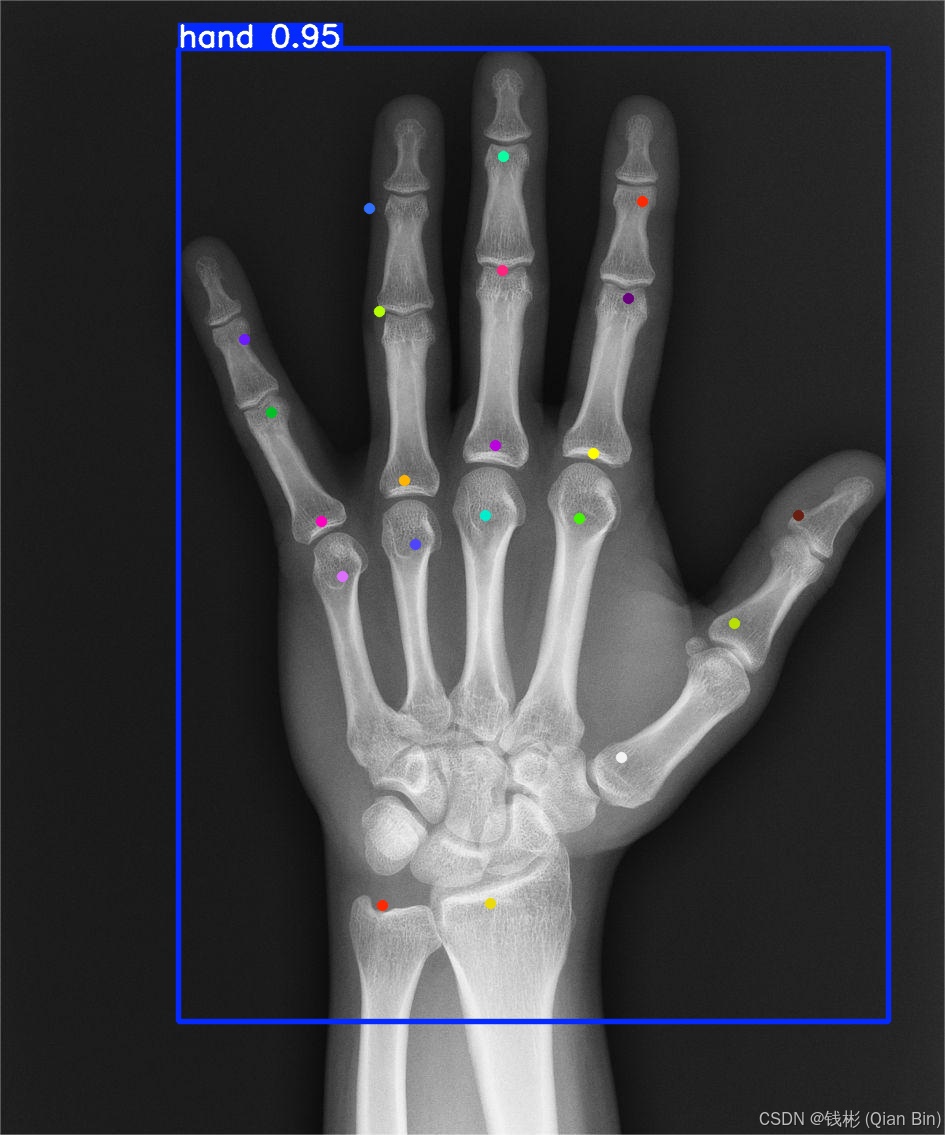

运行上述脚本后,在runs/pose中会生成redict文件夹,里面存放了对应的预测结果,如下图所示:

可以看到整体精度还是非常准的,后续通过使用更大的模型或者增加epoch的次数可以进一步提升精度。